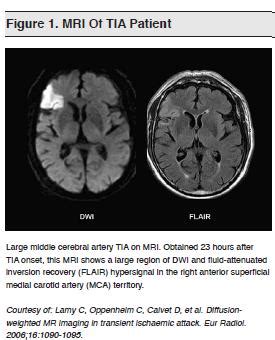

does mri always show tia